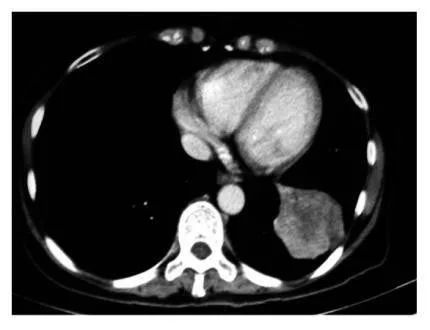

直到今年2月,Bryden的胸部和骨盆区域进行了CT扫描。她的肺部仍然没有癌症。

令医生惊叹的是,疫苗治疗6个月后,Magaly的肺部X光片显示肿瘤已经不见了。

美国专家前往古巴看望患者,疫苗注射半年后病灶被清除

这竟然惊动了美国罗斯威尔公园癌症研究所免疫学系主任Kevin Lee,他带着同事闻声前往古巴看望这位患者。他兴奋的说,“令人惊奇的是从看见明显肿瘤到肿瘤全部消失看见清晰的血管,这是非常了不起的”!